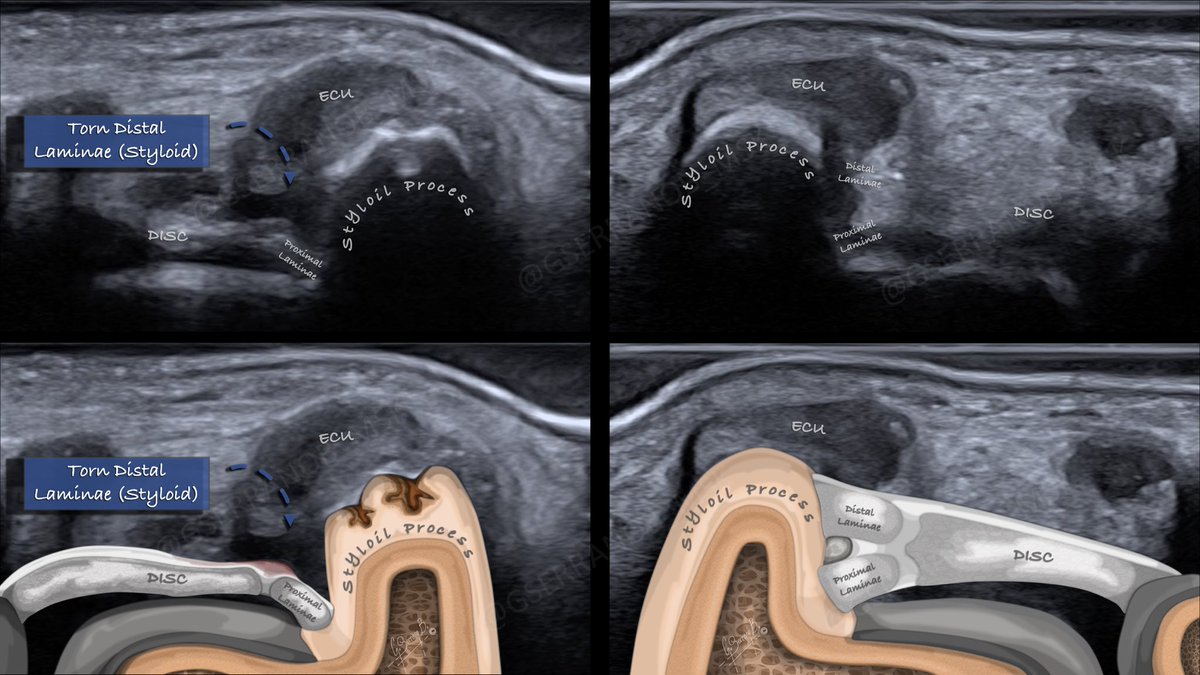

Gonzalo Serrano-Belmar.@GSERRANOB_MSK·

Complement to the previous TFCC case. This is what I came up with to obtain a coronal image of the TFCC to assess its peripheral insertion. We perform a maximum flexion of the wrist; in this way, we move the triquetrum and create a small window through which we can support the US transducer. It's important to flex the wrist in a neutral position to obtain the correct orientation of the peripheral TFCC, as we try to do when we do an MRI. We can also obtain a beautiful sagittal view by moving the transducer. #mskrad #MedTwitter